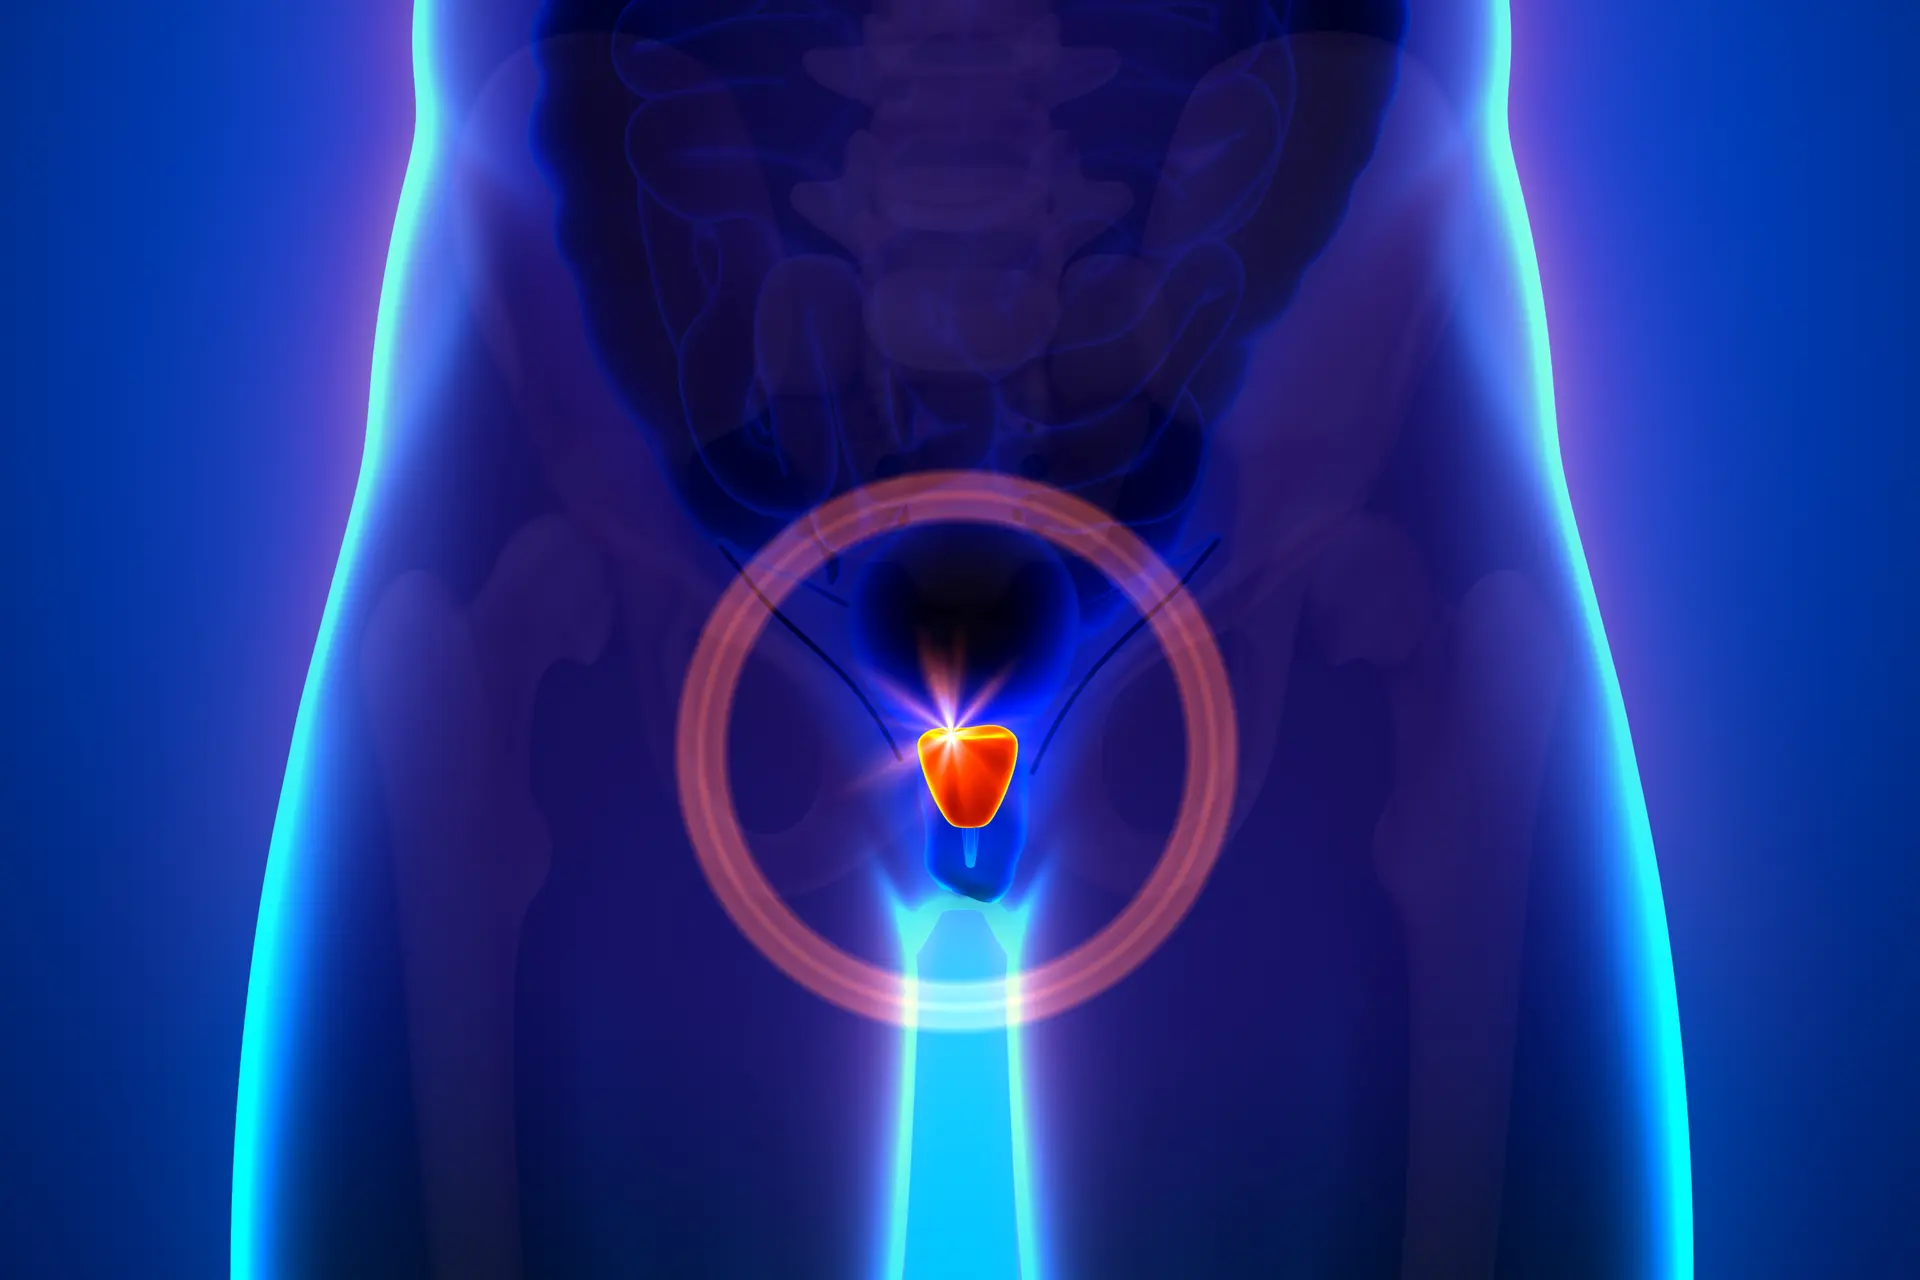

El tratamiento del cáncer de próstata a través de medios tradicionales como la cirugía o la radioterapia conlleva ciertos riesgos, y algunos pacientes experimentan impotencia, problemas urinarios y problemas intestinales, entre otros efectos secundarios no deseados. Sin embargo, pronto podrían estar sobre la mesa opciones de tratamiento más seguras y menos invasivas, incluida una nueva técnica de ultrasonido guiada por resonancia magnética que eliminó cánceres significativos en el 80 por ciento de los sujetos en un estudio de un año.

La nueva técnica se llama ablación por ultrasonido transuretral guiada por resonancia magnética (TULSA) y ha estado en desarrollo durante varios años. La tecnología mínimamente invasiva involucra una varilla que ingresa a la glándula prostática a través de la uretra y emite ondas de sonido altamente controladas para calentar y destruir el tejido enfermo, sin dañar el tejido sano.

Estas ondas provienen de 10 elementos calefactores incorporados a lo largo de la varilla para tratar toda la glándula prostática. Un algoritmo controla cuál de estos elementos emite las ondas de sonido en un momento dado, junto con su forma, dirección y fuerza. Todo esto tiene lugar dentro de un escáner de resonancia magnética, lo que permite a los médicos vigilar de cerca qué tejidos se calientan y cuánto.